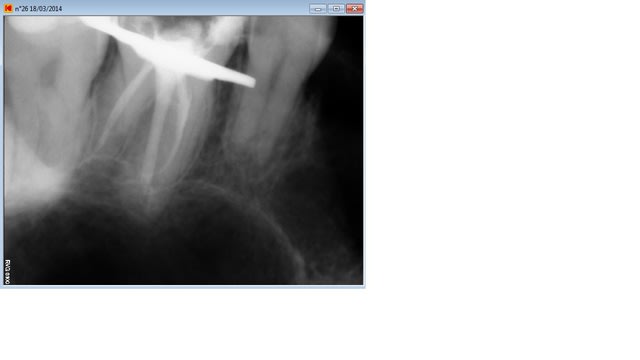

En voila deux supplémentaires, impossible de retrouver la dernière j'ai du l'enregistrer sur un autre dossier, je cherche ça.

On voit bien le cône dans le palatin qui bloque..

A vrai dire c'est surtout le palatin qui me gêne au niveau longueur, je trouve les deux autres pas trop mal (mis a part la condensation que je trouve encore très moyenne..)